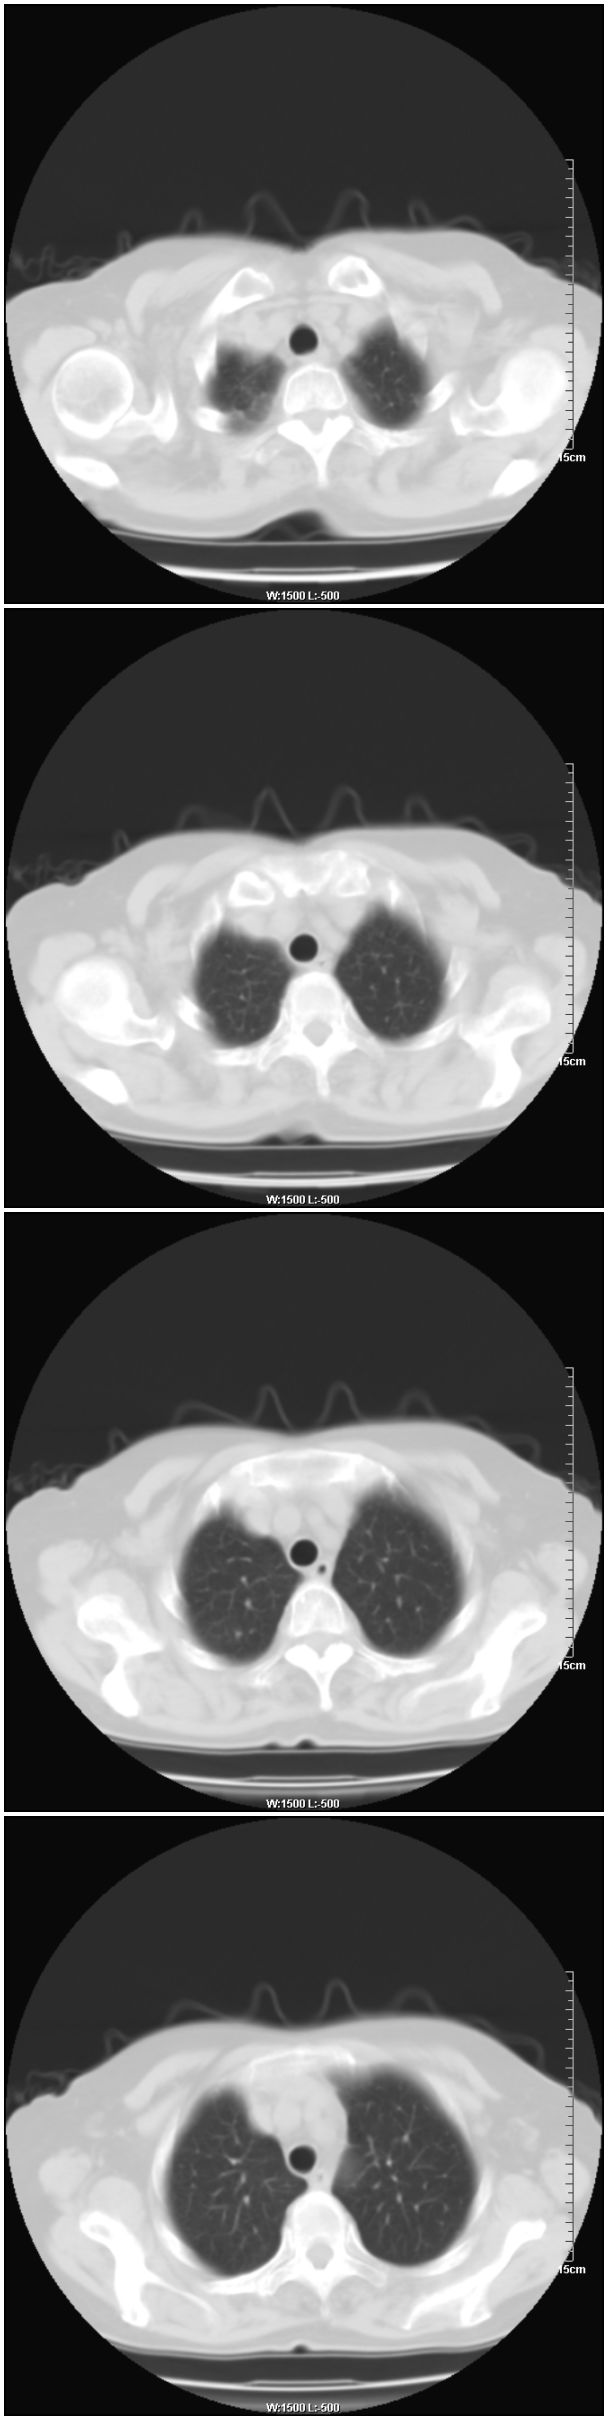

女性,78岁。术前体检发现肺部病变,看看还有什么问题?肺病变是什么性质?

右肺中心型肺癌可能

支持!右肺中叶中心型肺癌!右侧乳腺内上象限结节,建议薄扫

乳腺病变在右侧,右肺门区新生物伴右中叶阻塞性肺炎、部分部张

右肺中叶不规则肿块,管腔阻塞,心包内少量积液,支持右肺中心型肺癌。

应该是右肺中心型肺癌,乳腺的肿物应该在右侧,看见右侧有结节,并乳头凹陷

右侧乳腺内上象限结节影,边缘模糊,右肺病变相邻支气管内见软组织密度影及斑点样钙化灶,考虑肺癌可能性大,建议结合纤支镜检查。

右肺中央型肺癌伴中叶肺不张。